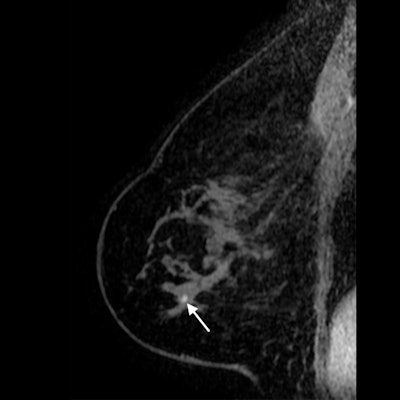

DBT has repeatedly proved its worth as a screening tool for women in the general population, but researchers have paid less attention to its use for cancer surveillance in women with a personal history of breast cancer. The new study suggests breast cancer survivors may see more benefit from alternative screening modalities, such as MRI.

Nevertheless, the researchers said their findings more readily support the use of MRI screening for women with a prior breast cancer diagnosis. The findings go to show that MRI continues to visualize cancers that mammography can't -- even in the DBT era.

"Given that the cancer detection rate did not significantly change after DBT integration and that one-third of interval cancers were detected at MRI, our results suggest that supplemental screening with MRI will continue to be useful in this high-risk population," the authors concluded.